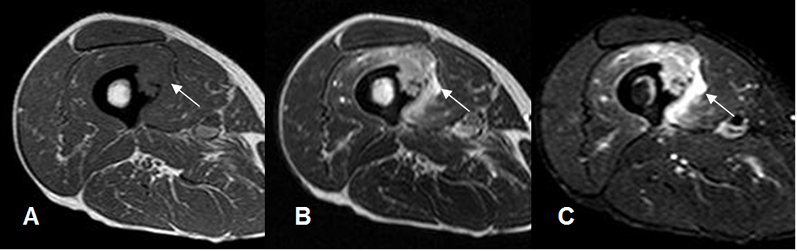

Fig 9. Lesión en RM.

A: RM axial en T1, B: RM axial en T2 y C: RM axial en STIR. Lesión de tejidos blandos en el muslo, que compromete la cortical, hipointensa en T1, hiperintensa en T2 y STIR.